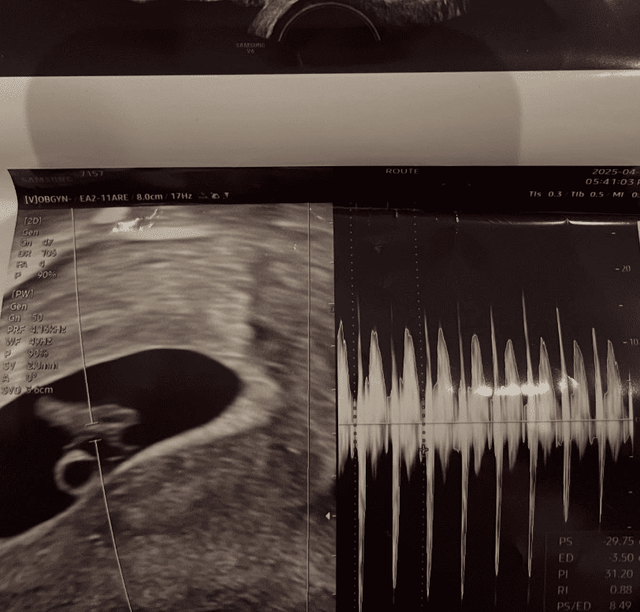

이와 함께 서민재는 남자친구와의 다정한 데이트 사진은 물론, 아기 초음파 사진과 함께 상대의 실명, 출신 학교, 회사 정보 등 구체적인 남친 신상까지 공개했습니다. 이 같은 파격적인 공개는 단순한 연애 고백이 아닌, 심각한 폭로로 이어졌다는 분석이 이어지고 있습니다.

2025년 5월 2일, 서민재는 남자친구와 함께 찍은 사진과 함께 “아빠 된 거 축하해”라는 글을 남기며 임신 사실을 처음 알렸습니다. 함께 게시된 사진 속에는 초음파 사진과 남자친구와의 다정한 모습이 담겨 있었고, 그녀는 남자친구가 “1997년생, 세종대 20학번”임을 밝히며, 그가 대학생임을 강조했습니다.